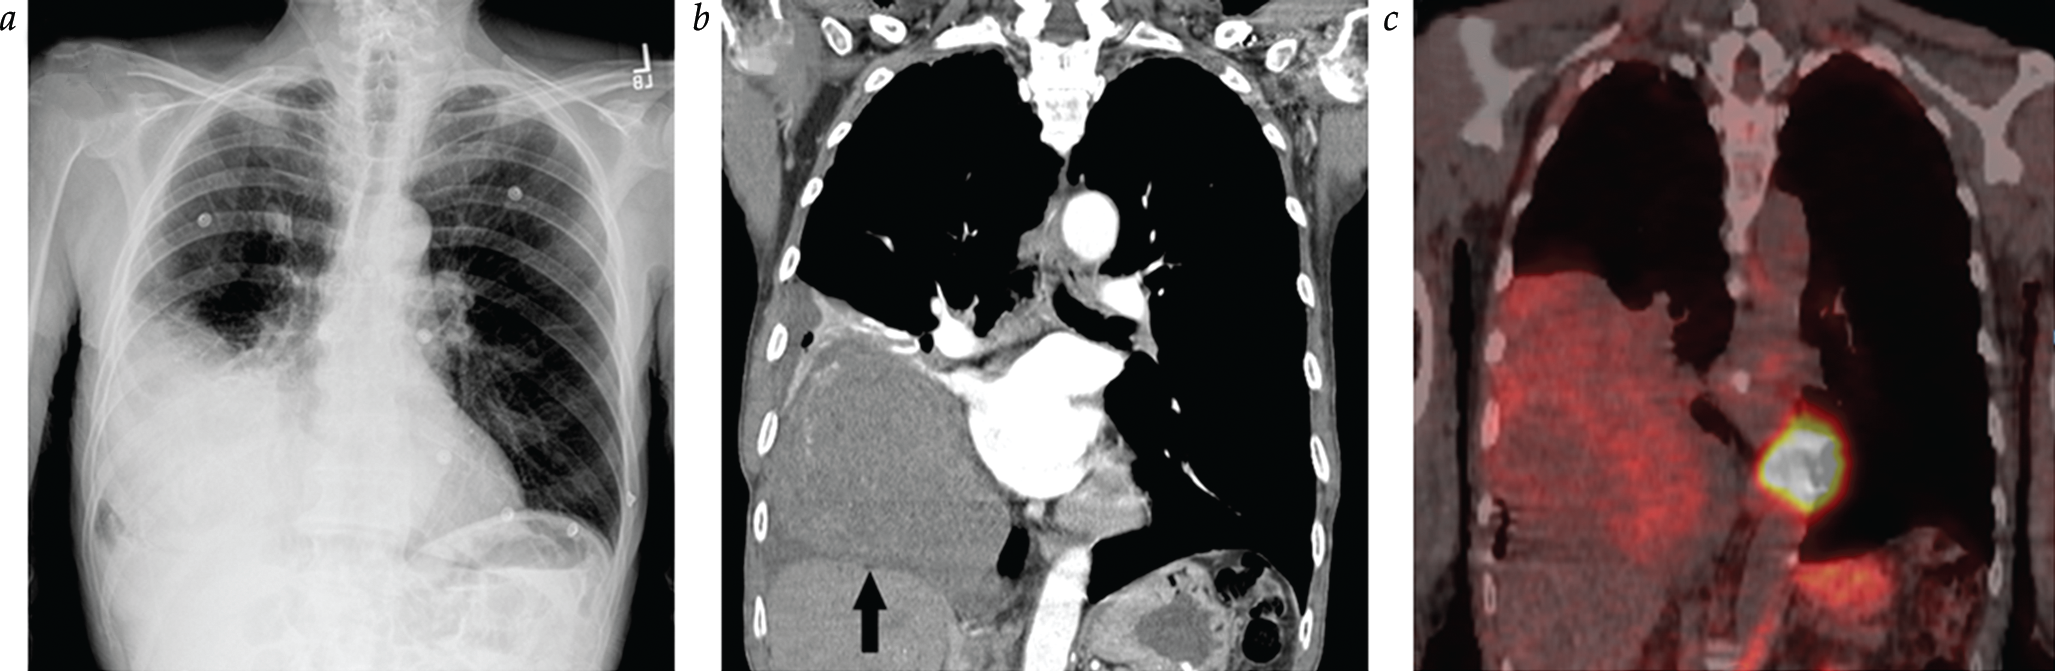

- Identification of the NAB2-STAT6 fusion as a key genetic aberration in SFTs

- Recognition of subsets of SFTs with more aggressive clinical behavior

- Development of a simple risk assessment model